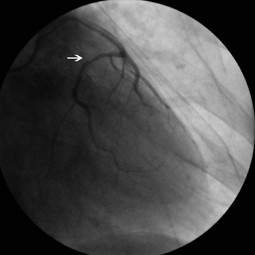

Fig. 2

Video 1. Right anterior oblique view shows that left main coronary artery originating from the proximity of the RCA and tracking an unusal direction to the left side and dividing into left anterior descending and left circumflex artery and LCx artery was totally occluded just after the division (avi 0,6MB)